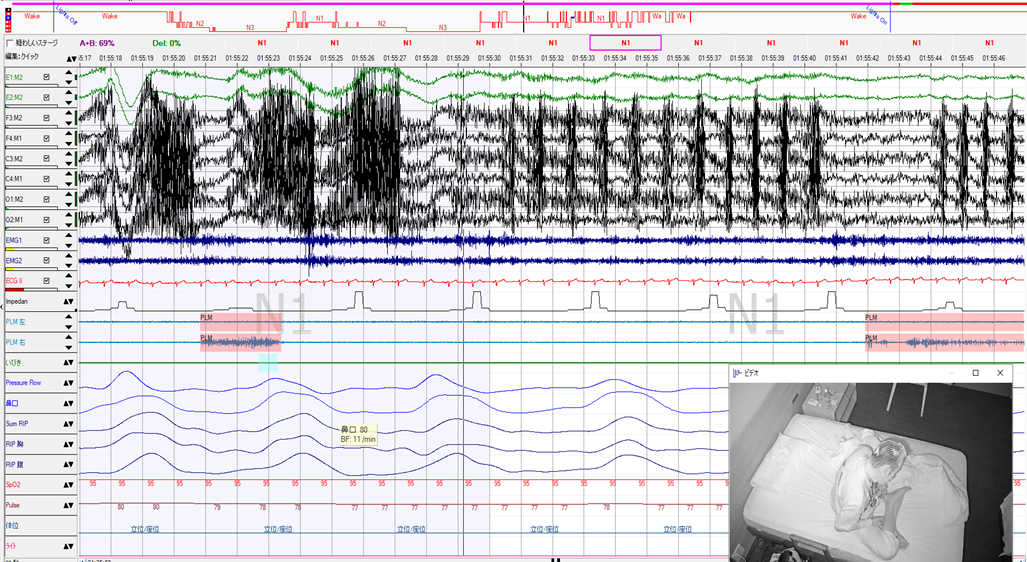

低換気とPLM、PVCが目立つ中等度SAS症例

60歳台 女性 身長:160㎝ 体重:66kg BMI:25.8 ESS:2 腰痛で受診したクリニックで、ついでに行った検査で動脈硬化を指摘されて、当クリニックを紹介受診されました。いびきの指摘と起床後に再度寝てしまうという訴えもあり、簡易検査を施行しました。REI=22.0回/時間、最低酸素飽和度が79%の結果で、診断PSGを行いました。AHI=25.8回…